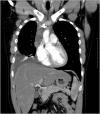

Adult lymphoblastic lymphoma (LBL) is an aggressive form of non-Hodgkin lymphoma occurring among predominantly adolescent and young adult men, accounting for 1%-2% of all non-Hodgkin's lymphomas. In contrast to B-LBL, T-cell LBL is much more common, accounting for up to 90% of disease in adults. Mediastinal mass, pleural and/or pericardial effusions are the major characteristics of T-LBL. We report an 27-year-old male with a pleural effusion, mediastinal lymphadenitis, and a normal hemogram. The cytology of the pleural effusion initially was lymphocytic exudative and ADA was high. For definitive diagnosis a medical thoracoscopy was done. The partial pleura showed multiple irregular nodules and thickening in sheets. It was picked and immunophenotypic study revealed the following: CD3, TdTþ, CD7 with Ki 67 index of 70-80%. The patient was finally diagnosed with T-LBL. He was treated with chemotherapy and is on regular follow up with resolution of effusion. The case highlight the point that medical thoracoscopy is a safe and accurate diagnostic procedure for pleural diseases, and partial pleura biopsy yielded the correct diagnosis.